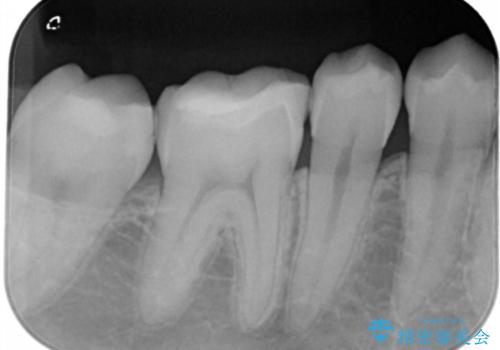

- 右上下6番の銀歯のやり変えを希望された患者様です。

切削量・形態を考慮し、上はセラミッククラウン、下はセラミックインレーでの治療を選択しました。

上はう蝕が歯頚部まで達していたのでクラウンでの治療を選択しました。

銀歯直下もう蝕が進行していたので全て除去した上でCRにて裏層しています。

下はクラウンほど切削量が多くないと判断し、インレーでの治療を選択しました。